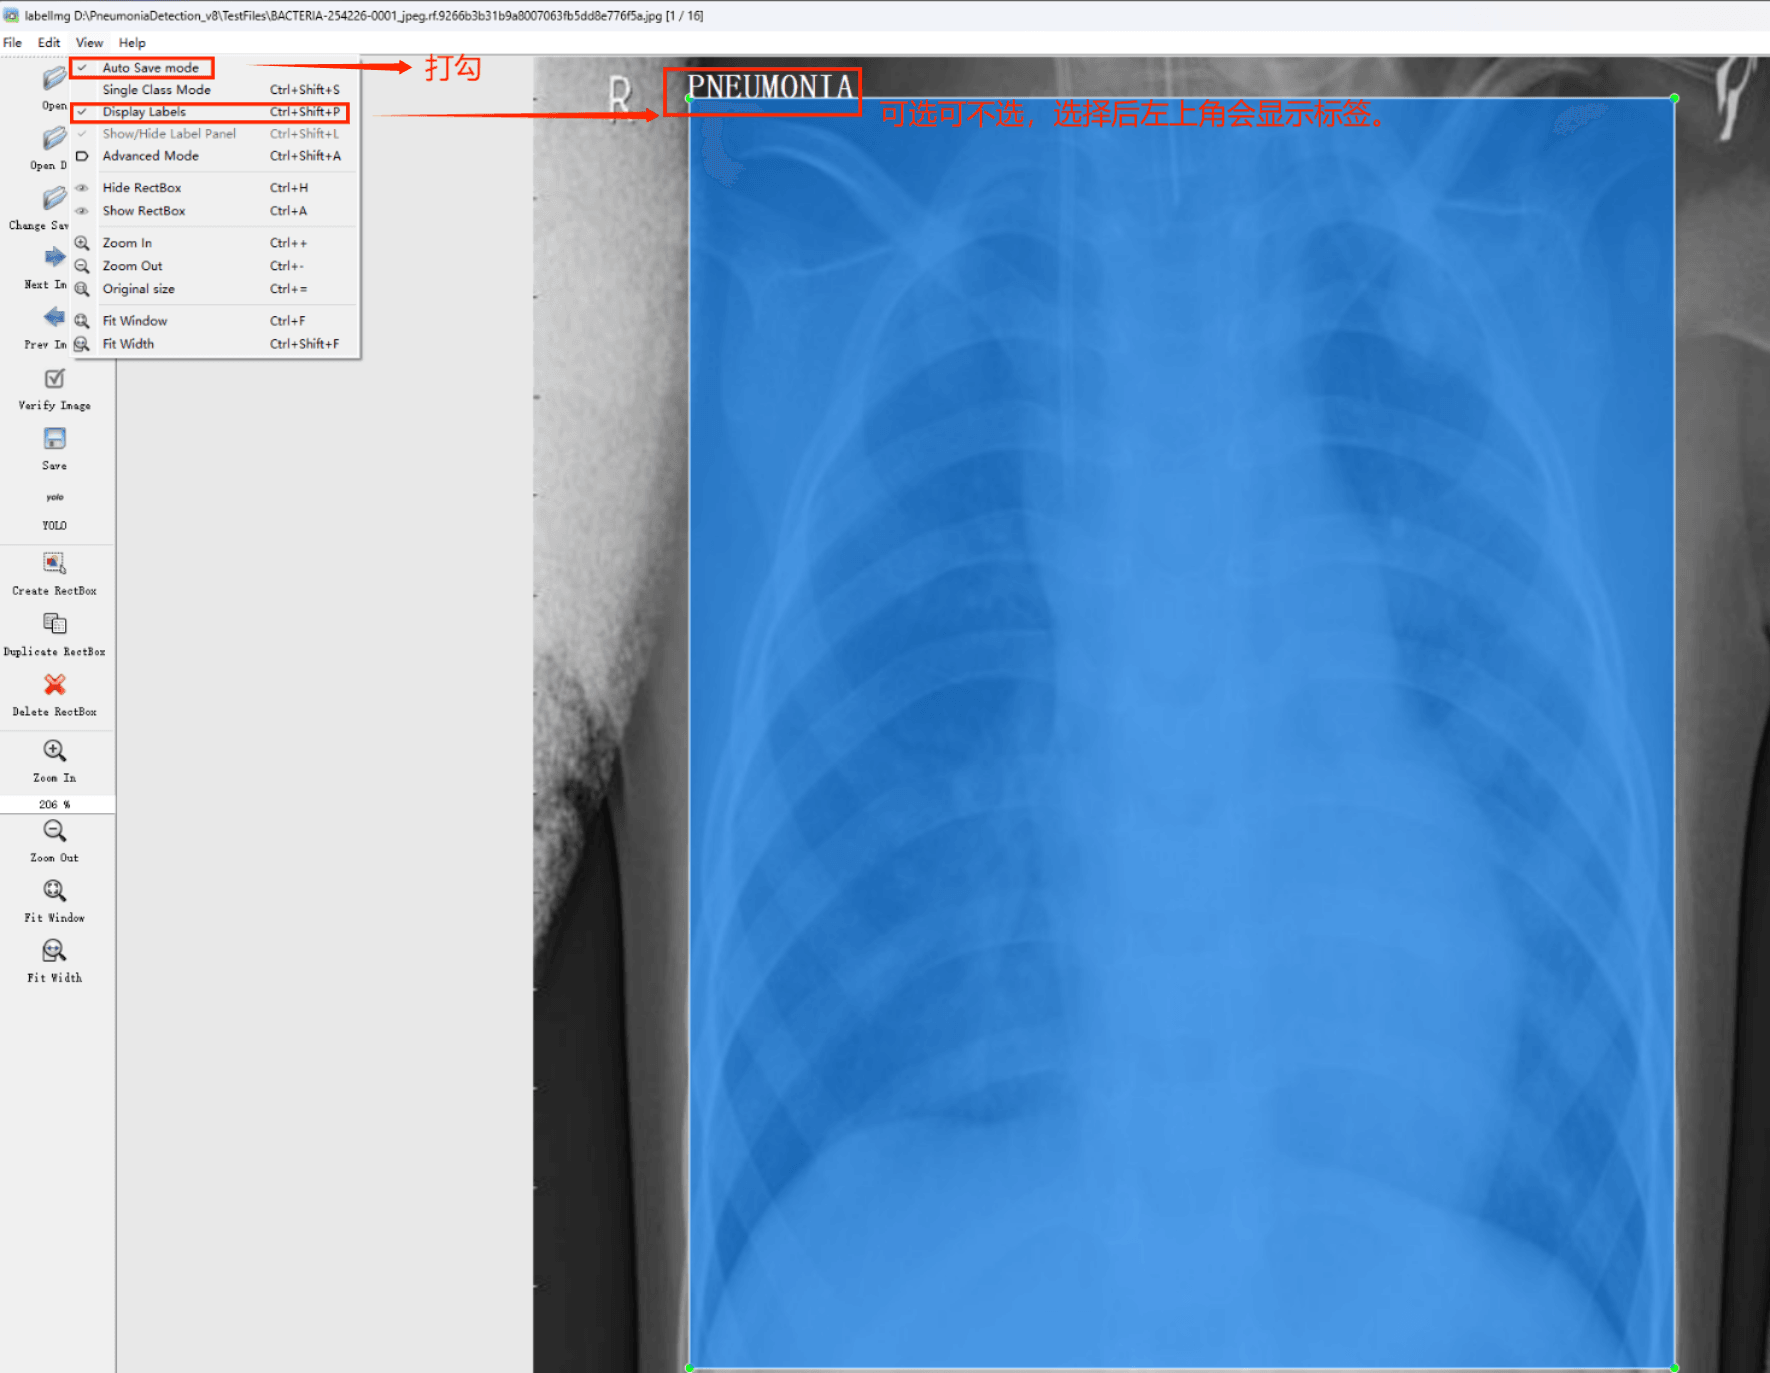

目标检测标注工具

(1)labelimg:开源的图像标注工具,标签可用于分类和目标检测,它是用python写的,并使用Qt作为其图形界面,简单好用(虽然是英文版的)。其注释以 PASCAL VOC格式保存为XML文件,这是ImageNet使用的格式。此外,它还支持 COCO数据集格式。

初识labelimg

打开后,我们自己设置一下

在View中勾选Auto Save mode

接下来我们打开需要标注的图片文件夹

并设置标注文件保存的目录(上图中的Change Save Dir)

接下来就开始标注,画框,标记目标的label,然后d切换到下一张继续标注,不断重复重复。